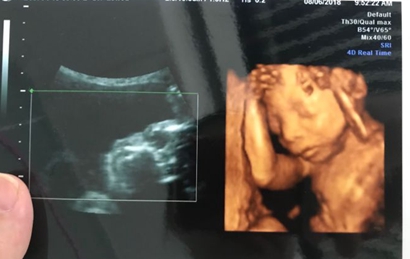

一:在彩超单上会印,顶头最右边有两行字,是英文字母和数字组成的,第一行是日期,第二行是时间,如果第一行是M开头,那就是male男,如果是F开头就是female女,第二行打头的T是时间的意思。

二:彩超单上通常有“双侧肾盂分离”,那90%是男孩;如果是“双侧肾盂未见明显分离”,那95%是女孩。

三:彩超单上很小英文字母Qual high 1是女孩,2是男孩。

四:通过四维彩超图看清胎儿性别,在六个月以后照四维彩超,只要宝宝的姿势是正面不是给个背影什么的,是男是女一看就知道。不过因为国家明文规定不能查胎儿性别,所以医生不会把能明显看出性别的一面照给妈妈看。